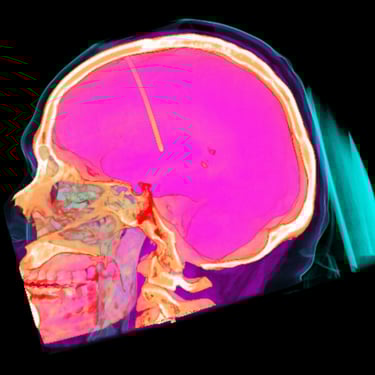

Hidrocefalia: Tratamiento mediante Derivación Ventriculoperitoneal

La hidrocefalia es una condición caracterizada por la acumulación anormal de líquido cefalorraquídeo en los ventrículos cerebrales, lo que genera aumento de la presión intracraneal y síntomas como cefalea, náuseas, alteraciones cognitivas y trastornos de la marcha. Cuando el manejo médico no es suficiente, la derivación ventriculoperitoneal (DVP) es el tratamiento quirúrgico más utilizado. Este procedimiento permite drenar el exceso de líquido desde el cerebro hacia la cavidad abdominal, donde es reabsorbido, aliviando la presión intracraneal y mejorando la función neurológica. El tratamiento oportuno es clave para prevenir secuelas.